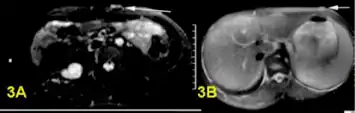

Image of neurofibroma showing myxoid appearance